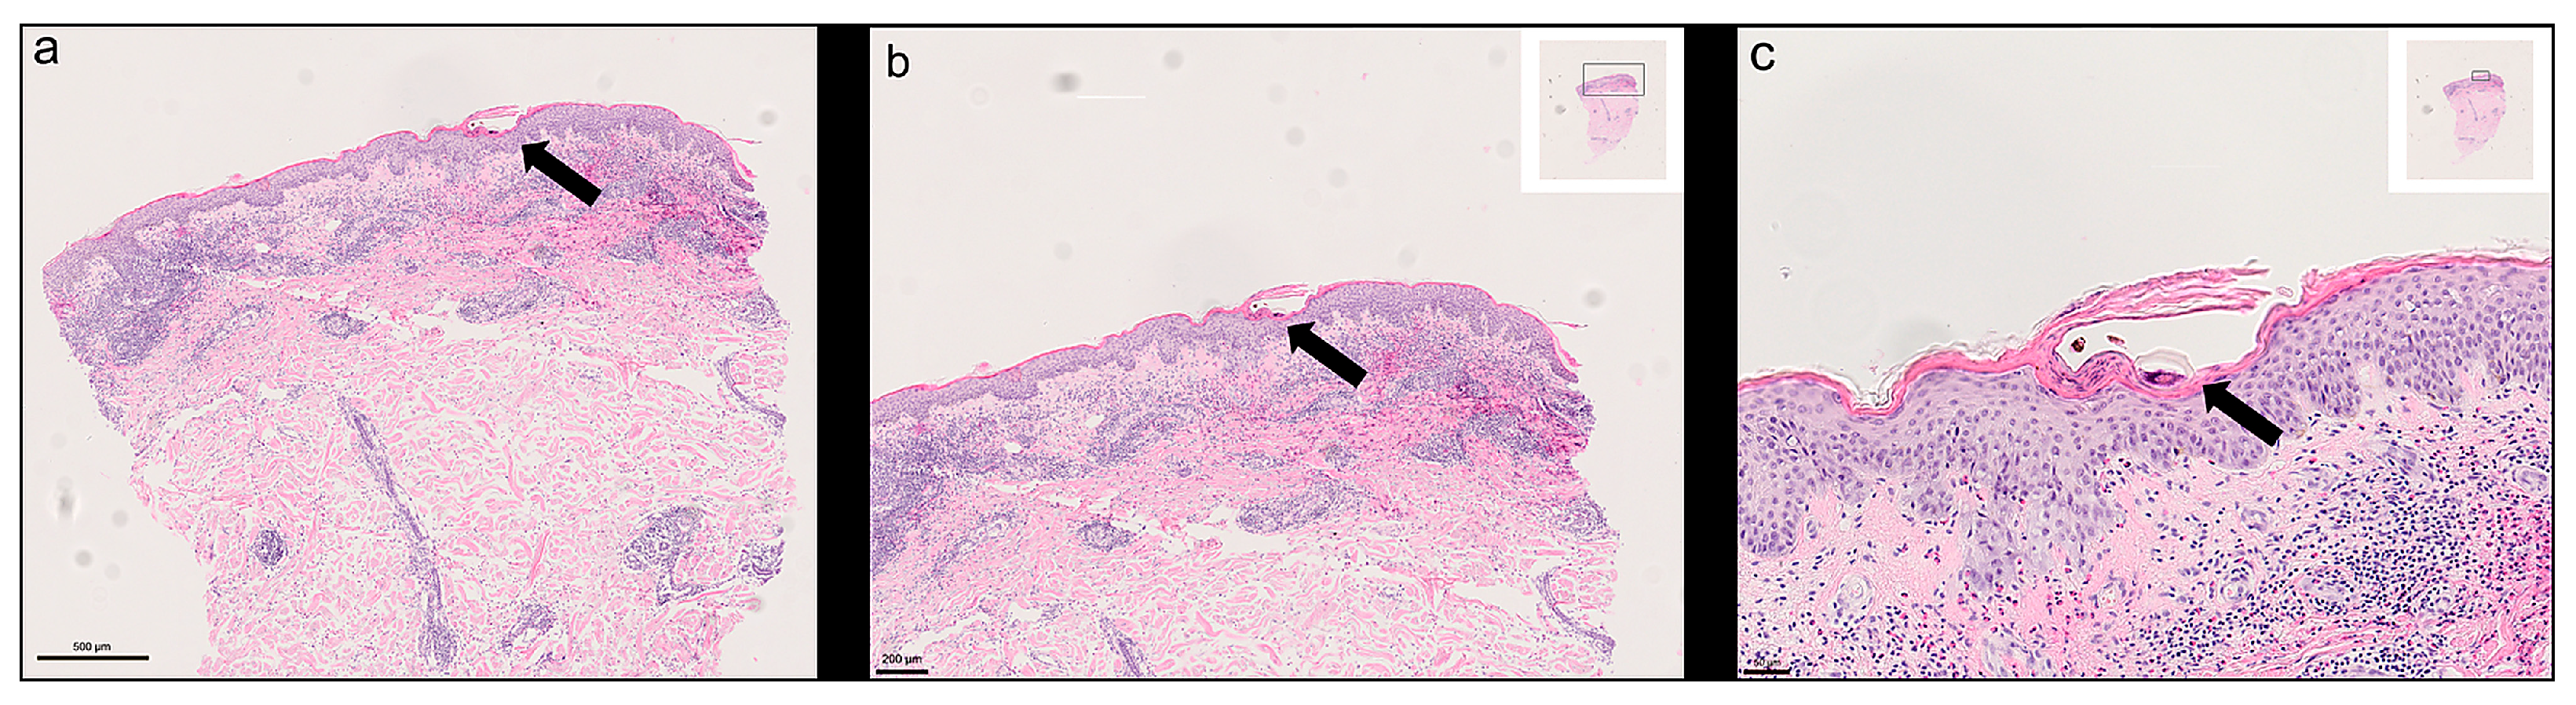

Routine histology consistently demonstrated S. scabiei mites or mite remnants, including chitinous exoskeleton fragments and scybala (faecal pellets), in the stratum corneum. In most cases, the epidermis showed marked reactive changes with compact hyperkeratosis, parakeratosis, and occasional intracorneal vesicles. The underlying dermis frequently contained a dense perivascular and interstitial inflammatory infiltrate composed of lymphocytes, histiocytes, and numerous eosinophilic granulocytes, in keeping with a hypersensitivity pattern. Figure 1 illustrates typical histopathological features from one case study at increasing magnifications, including intact mites embedded in the hyperkeratotic stratum corneum and the associated inflammatory reaction. Histopathological features were consistent with those previously reported for this cohort [10].

Figure 1. Histological features of scabies in HE-stained tissue sections. (a) Overview showing hyperkeratosis and epidermal hyperplasia with embedded mite structure; (b) Intermediate magnification revealing one mite in the stratum corneum and underlying inflammatory cell infiltrate; (c) High magnification of S. scabiei in the surrounding keratin layer. Scale bars are shown in the images—image taken from one of the study cases included in this report.